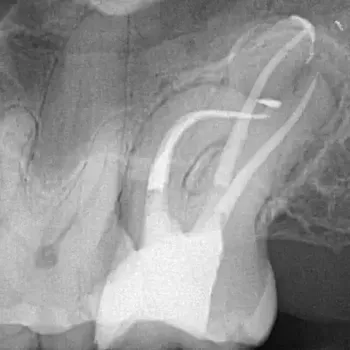

Fall 2: Entfernung eines Instrumentenfragmentes

Röntgenbild: Instrumentenfragment Ausgangssituation

Ausgangssituation

Röntgenbild: Instrumentenfragment Kontrolle nach Wurzelfüllung

Kontrolle nach Wurzelfüllung